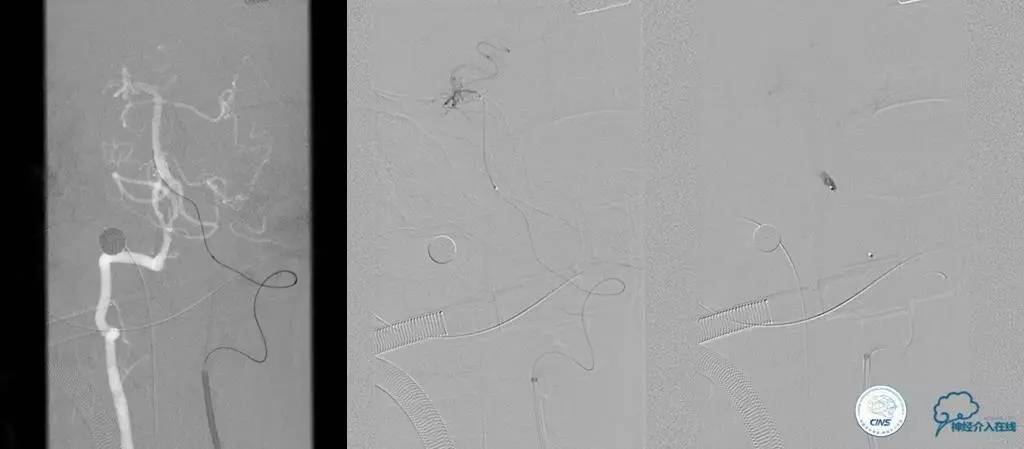

再通技术简要步骤

1.微导丝探查、穿过闭塞段(轻柔!)

2.微导管过闭塞段后必须造影确认在血管真腔

3.交换微导丝,撤出微导管

4.球囊预扩(原则:缓慢充盈,从小到大)

5.支架成形(保证系统稳定)

注:释放支架前及术后3天严格控制收缩压<120mmHg